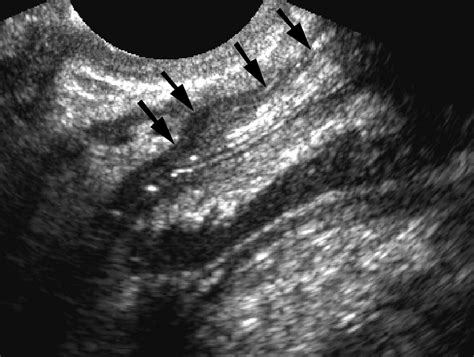

During a consultation, a colorectal surgeon will perform a physical examination. In some cases, they may use diagnostic imaging to visualize the tract that cannot be seen with the naked eye. Procedures such as endorectal ultrasound or pelvic MRI are far more informative than general Rectal Fistula Images found on public forums, as they provide a clear map of the anatomy for the surgeon.